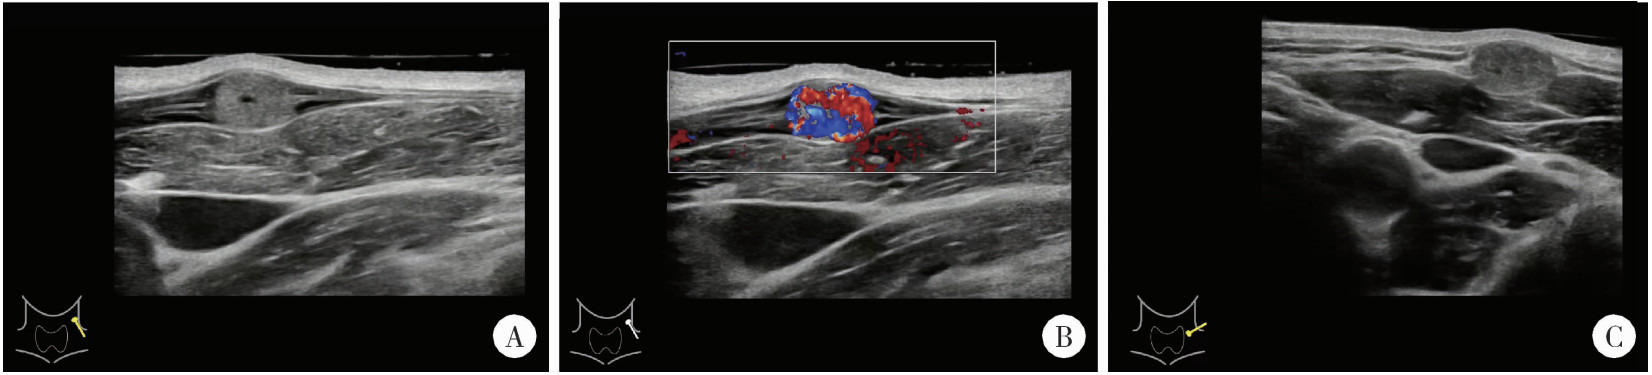

Figure 1

Ultrasound imaging of the patient with IPEH A, a hypoechoic nodule with clear, incompressible borders was seen in a local superficial vein; B, color doppler imageing shows rich blood flow signal; C, adjacency of the nodule to the surrounding neck vessels.IPEH, intravascular papillary endothelial hyperplasia."